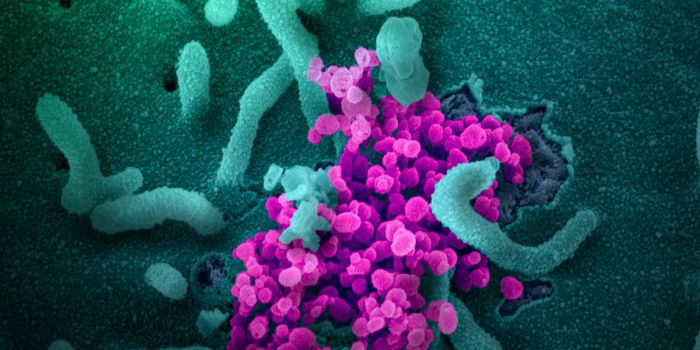

SEP 25, 2021Health & MedicineAfter a year-long study, researchers have assembled a detailed narrative about how the SARS-Cov-2 virus has spread on th ...